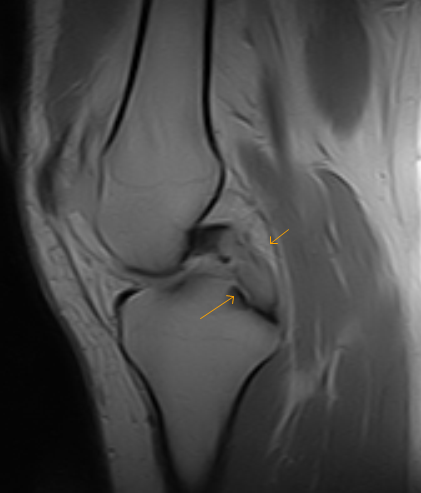

Shows normal ACL and PCL. | Download Scientific Diagram

Intact PCL on sagittal MRI T1 sequence | Download Scientific Diagram

MRI of normal PCL, absent ACL and posterior loose bodies - Arizona